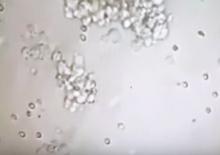

သုတ်ရည်ထဲတွင် သုတ်ပိုးမပါရှိသော အမျိုးသားများ သားသမီးရရှိစေရန် မျှော်လင့်ချက်များ မကုန်ဆုံးသေးပါ။

အောက်တွင် post လုပ်ထားသော video ဖိုင်လေးထဲကလို ကပ္ပယ်အိတ်အတွင်းမှ အသားစထဲရှိ ရှင်သန်သော သုတ်ပိုးကို အသုံးပြု ၍ ဖန်ပြွန်သန္ဓေသားနည်းပညာဖြင့် သားသမီးရရှိအောင် ကြိုးစား နိုင်သည့်သတင်းကောင်းကို တဖန်ပြန်လည်၍ တင်ပြလိုက်ပါတယ်။

This is the movie how we do it!